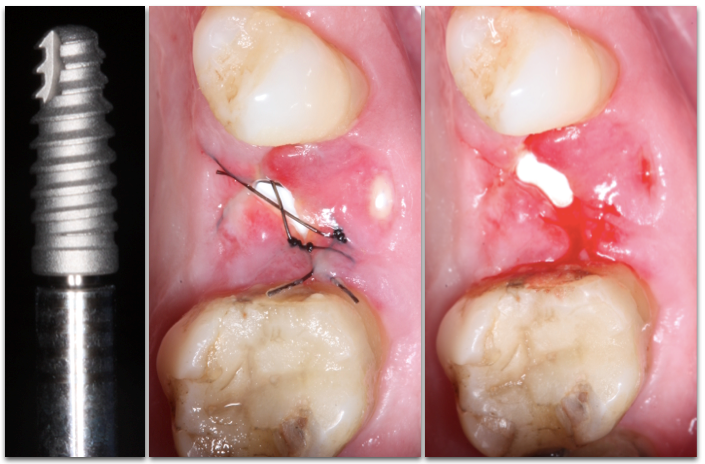

Paciente L.M., 53 anos, apresentava sensibilidade durante a mastigação e relatava mau hálito na região do dente 25. Durante análise clínica, a paciente apresentava sorriso alto (Figura 1). Após análise tomográfica, foi constatada uma perfuração radicular no dente em questão e que a raiz estava em contato com a tábua vestibular, sendo que esta possuía ≥1mm de espessura em seu terço cervical (Figura 2). Após a paciente concordar com o plano de tratamento, foi realizado a instalação imediata de um implante Cone Morse de corpo cônico (Due Cone 3.5×11, Implacil De Bortoli, São Paulo, Brasil), regeneração óssea guiada com osso bovino inorgânico e colocação de uma barreira regenerativa de politetrafluoretileno denso.

O implante Cone Morse de macro-geometria cônica foi instalado 2mm infra-ósseo. Este tipo de plataforma (platform switching) possui vantagens mecânicas e biológicas quando comparado com os implantes HE e HI. Mecanicamente, quando o pilar protético é submetido à forças que simulam a mastigação, existe pouca ou nenhuma micro-movimentação do pilar. Esta característica é fundamental para a não formação de um micro-espaço entre o pilar e a plataforma do implante, protegendo assim o sistema contra a micro-infiltração bacteriana. Com relação à vantagem biológica, pode-se citar o menor diâmetro do componente protético em relação à plataforma do implante. Assim sendo, a crítica zona de contaminação localizada entre o implante e o pilar fica localizada distante do tecido ósseo, gerando assim um vedamento biológico e consequente manutenção do tecido ósseo peri-implantar em longo prazo.

Implantes de macro-geometria cônica são altamente indicados em casos de implante imediato pois a conicidade do implante facilita a obtenção da estabilidade primária, crucial para o sucesso da osseointegração. Neste caso, a obtenção de uma boa estabilidade inicial também foi facilitada pelo posicionamento da raiz no alvéolo (Classe I) (Kan et. al 2011). Com a raiz voltada para a tábua vestibular, após a remoção do dente o osso palatal remanescente propiciou condições para o travamento por causa de sua anatomia mais corticalizada.